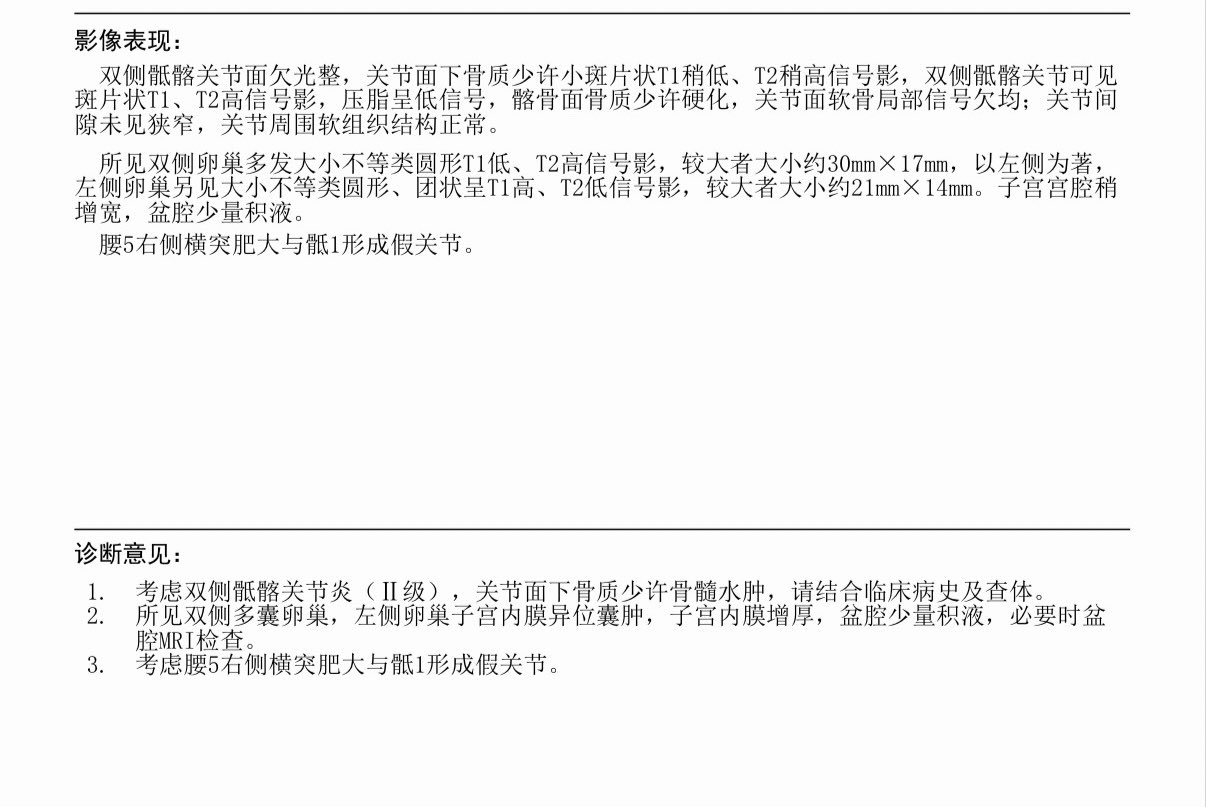

地狱难度…救救我TT

目前好像还没有找到能治好的办法,脊椎的疼痛和内异症的都是。有一个关键字为血小板的治疗3k一针…不知道要做多少次,而且似乎也不确定效果

☯️🧬霊狐製作所 公式ツイッター @Cheese_Ghostfox@AnIncandescence 富血小板血浆注射?

2026-03-03T16:41:47.000Z

看到那个「关键字」狐第一个想到的疗法

炽烈已极 @AnIncandescence@Cheese_Ghostfox 查了一下感觉可能符合..!狐好厉害

炽烈已极 @AnIncandescence@Eternal1uv9 明确是先天性发育异常,Bertolotti综合征

2026-03-04 16:00:35 UTC

炽烈已极 @AnIncandescence@Eternal1uv9 假关节把额外负荷传到骶髂关节可能形成了炎症,这是继发影响。后天生活(应该和我的专业有关)导致了加重

炽烈已极 @AnIncandescence@bghtnya 我的问题应该算一种解剖学上的变异。 https://t.co/IM6neHUG3x

炽烈已极 @AnIncandescence@RicardoKangAn 你在说什么。。脊柱侧弯?就算脊柱侧弯也不会让腰5右侧横突肥大与骶1形成假关节也不会让双侧髂骨关节面下骨质密度增高